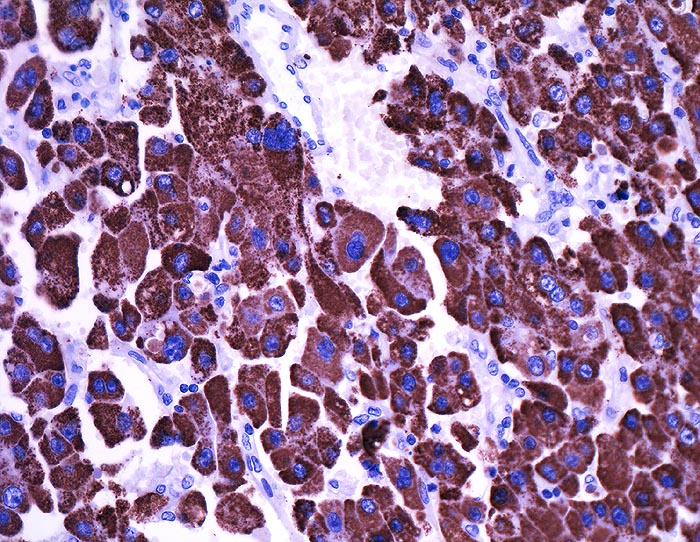

Hep Par 1 (Hepatocyte Paraffin 1)

Anfärbung:

Zytoplasma grob granulär ohne canaliculäre Akzentuierung.

Reaktion im Normalgewebe:

Nicht neoplastische Hepatozyten sind diffus positiv. Regenerative Knoten zeigen eine heterogene Anfärbung. Normale Dünndarmschleimhaut kann fokal stark positiv sein. Alle anderen Normalgewebe sind negativ.

Reaktion in Neoplasien:

Hepatozelluläre Karzinome färben sich heterogener an als das Normalgewebe. Die Anfärbung korreliert nicht mit dem Differenzierungsgrad. Kombinierte hepatozelluläre und cholangiozelluläre Karzinome sind lediglich in der hepatozellulären Komponente positiv.

Gallenwegskarzinome, Pankreaskarzinome und Magenkarzinome sind selten positiv.

Diagnostischer Nutzen:

Unterscheidung des hepatozellulären Karzinoms vom cholangiozellulären Karzinom und von Lebermetastasen.